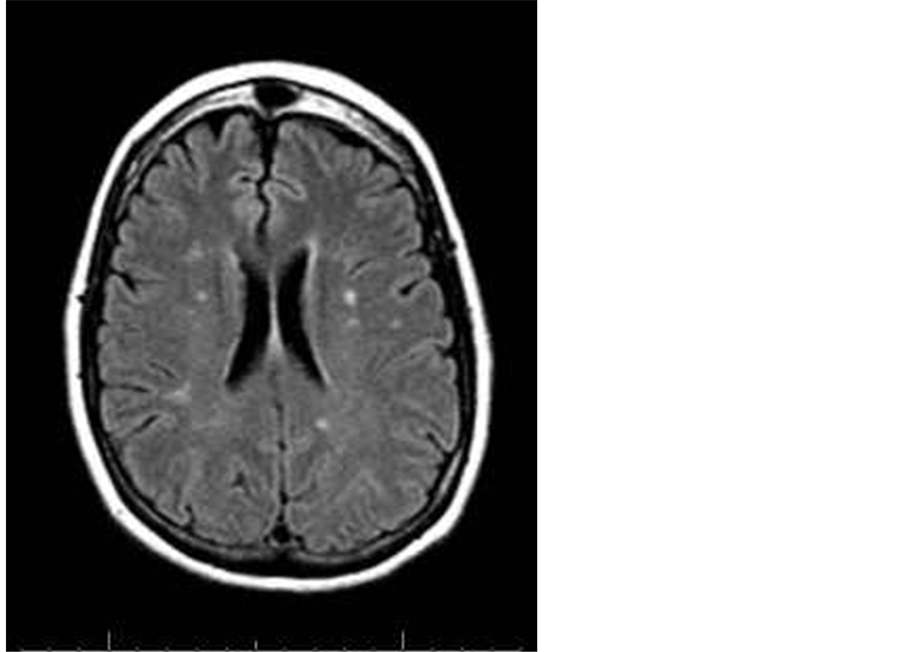

Demographic: With regards to gender, 60 patients (75%) were male and 20 patients (25%) were female. The mean group age was 42.4 years. Criteria and distribution of MRI brain lesions are described in Table 1, Figure 1, Figure 2 and Figure 3.

From the table we noticed that 50% of cases (24/48) had silent cerebral infarctions with periventricular white matter distribution, 33.3% (16/48) had infarcts in the basal ganglia and 16.66% had infarction in the thalamus.

Figure 2. A 63-year-old male patient with multiple head of caudate and posterior periventricular infarctions of high FLAIR signal.